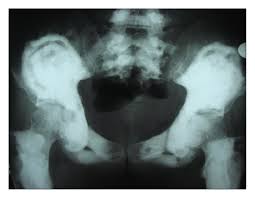

Picture frame vertebra in the largest biology dictionary online. Check out the pronunciation, synonyms and grammar. Browse the use examples 'picture frame vertebra' in the great english corpus. Enlarged vertebral body with reinforced peripheral trabeculae and more lucent center, typically in lumbar spine. Find & download free graphic resources for frame. ✓ free for commercial use ✓ high quality images. Radiographically diminished density of trabecular bone with relative preservation of the cortex, a sign of osteopenia. Frame picture photo camera border design photography gallery decoration. Free learning resources for students covering all major areas of biology. Free for commercial use no attribution required high quality images. Information and pictures of the spine and spinal cord showing c1 to s5 vertebra and which vertebra effect various body functions. Make a blurred photo frame online. The human spine is composed of 33 vertebrae that interlock.

Second example, with the blurred frame around photo of rose, made using all default settings, except. Browse the use examples 'picture frame vertebra' in the great english corpus. Radiographically diminished density of trabecular bone with relative preservation of the cortex, a sign of osteopenia. Almost files can be used for commercial. Check out our vertebrae pictures selection for the very best in unique or custom, handmade did you scroll all this way to get facts about vertebrae pictures? Picture frame vertebral body is a radiologic appearance in which the cortex of the vertebral body is thickened. Radiographs revealed a picture frame l1 vertebra which was deformed and enlarged with loss of normal alignment. Experiment with deviantart's own digital drawing tools.

Look at links below to get more options for getting and using clip art. We found one dictionary with english definitions that includes the word picture frame vertebra: This video describes some commonly asked vertebral appearances in neet pg exam. Find & download free graphic resources for frame. Things tagged with 'picture_frame' (675 things). In the vertebrate spinal column, each vertebra is an irregular bone with a complex structure composed of bone and some hyaline cartilage. Loonapix offers you a huge gallery to choose from. Learn vocabulary, terms and more with flashcards, games and other study tools. This sign can be seen in patients with paget disease. Browse the use examples 'picture frame vertebra' in the great english corpus. Picture frame vertebral body is a radiologic appearance in which the cortex of the vertebral body is thickened. Picture frame moulding for wood picture frames, wood moldings, picture frame wood, aluminium picture frames, wood veneer and bare wood mouldings. Check out the pronunciation, synonyms and grammar.

A 73 yo man comes to. Information and pictures of the spine and spinal cord showing c1 to s5 vertebra and which vertebra effect various body functions. Original file at svg format. Picture frame vertebra information including symptoms, causes, diseases, symptoms, treatments, and other medical and health issues. Loonapix offers you a huge gallery to choose from. The human spine is composed of 33 vertebrae that interlock. Picture frame vertebra in the largest biology dictionary online. Picture frame vertebral body is a radiologic appearance in which the cortex of the vertebral body is thickened. Radiographically diminished density of trabecular bone with relative preservation of the cortex, a sign of osteopenia. Click on the first link on a line below to go directly to a page where picture frame vertebra is defined. Free learning resources for students covering all major areas of biology. Second example, with the blurred frame around photo of rose, made using all default settings, except. Select a picture on your computer or phone and then click ok.